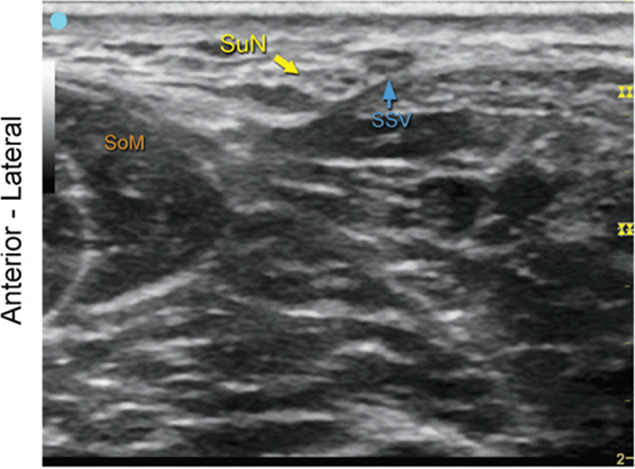

Sural Nerve at the Ankle

FIGURE 7.63.1A Ultrasound transducer position to image the sural nerve at the ankle.

FIGURE 7.63.1B Ultrasound image of the sural nerve at the ankle.

FIGURE 7.63.1C Labeled ultrasound image of the sural nerve at the ankle.

FIGURE 7.63.1D Labeled cross-sectional anatomy of the sural nerve at the ankle.

Abbreviations: SuN, Sural nerve; SSV, Small Saphenous Vein; SoM, Soleus Muscle; Lat. Mall., Lateral Malleolus.